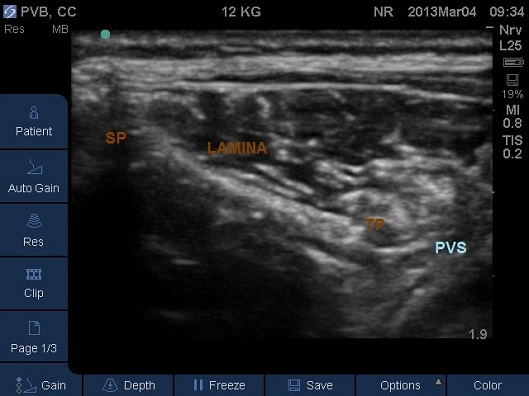

- Move the probe laterally in this plane and view the lamina and lateral to this the hyperechoic transverse process (TP) with acoustic shadow beneath (Fig 7,8)

Fig 7. Transverse Plane Mid-Thoracic level. PVS – paravertebral space, SP – spinous process, TP – start of transverse process.